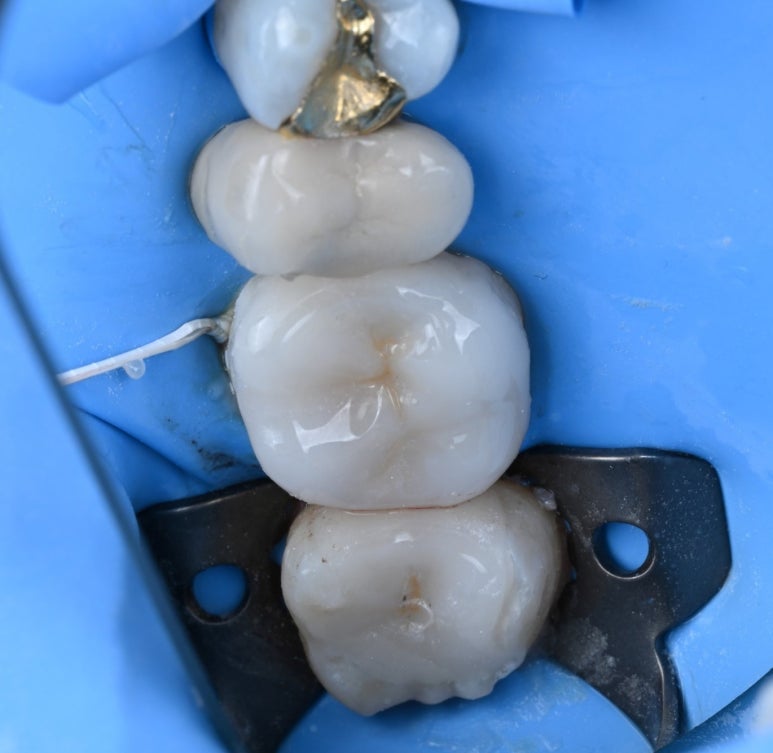

25.11.19 접착 준비

다시 한번

러버댐을 장착한 상태에서 정밀하게 접착을

마무리해 드렸습니다.

25.11.19 접착 후

25.11.19 교합조정까지 마친 후